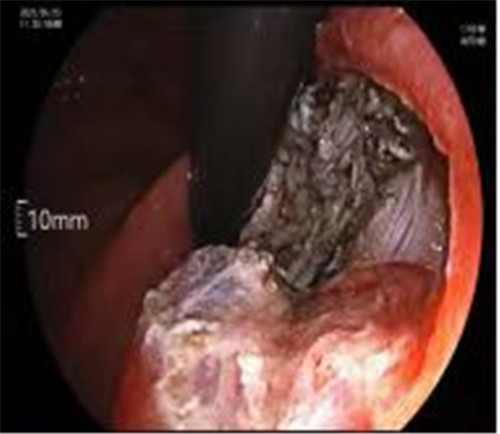

通過(guò)內(nèi)鏡切開(kāi)瘤體表面粘膜,分離后挖除瘤體,或以消化道全層切除的方法切除瘤體,并在內(nèi)鏡下縫合切口。與傳統(tǒng)手術(shù)相比,該項(xiàng)技術(shù)利用了人體自然通道,不會(huì)破壞人體結(jié)構(gòu),更加微創(chuàng)。不超過(guò)3cm向消化道腔內(nèi)生長(zhǎng)為主的良性或低度惡性粘膜下腫瘤(如間質(zhì)瘤、類癌、平滑肌瘤等),都可采用ESE治療。

近期病例之一,圖片依次為:胃鏡、超聲胃鏡、ESE術(shù)中、術(shù)后、切下病變。